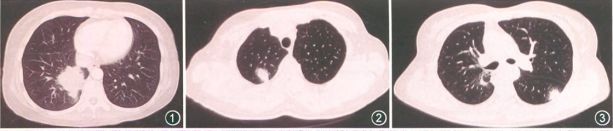

1. 实性结节型

单发或多发的结节状实变影,边界不清,常疑为肿瘤性病变。

2. 支气管血管束型

支气管血管束及小叶间隔增厚,可伴小囊腔形成。

3. 肺泡间质型

双肺磨玻璃影或条索状阴影,可伴有支气管血管束增粗弥漫网格影,伴支气管扩张症。

4. 圆形磨玻璃影型